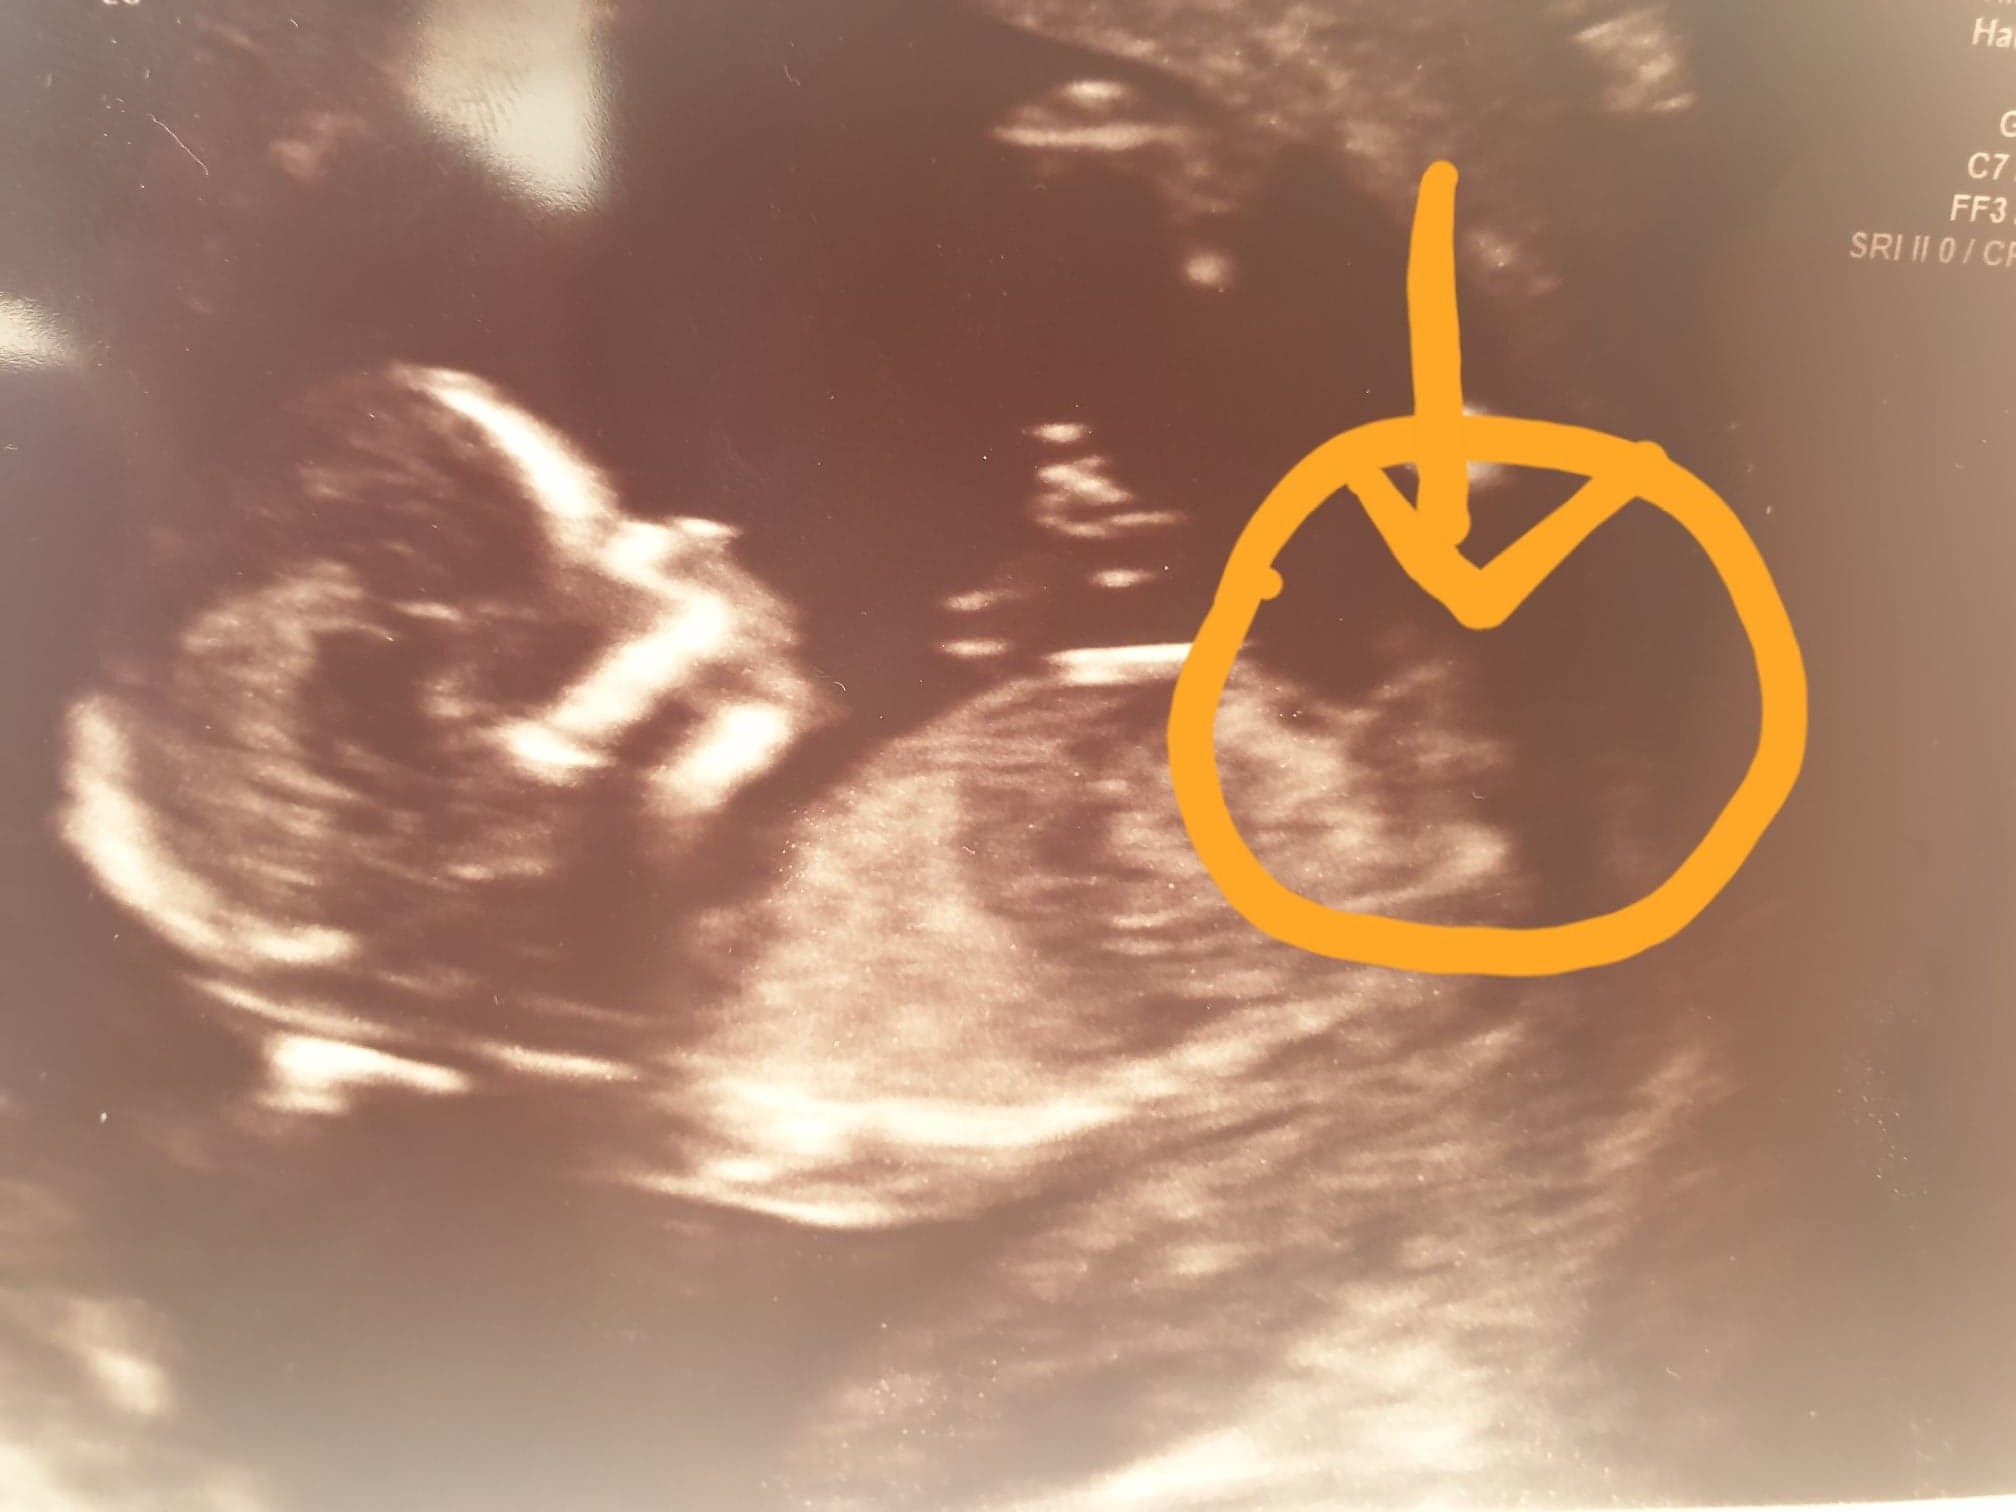

Witam, a to moje usg z 14tc co myslicie jaka pleć??

Załączniki

• scan.jpg

scan.jpg

165,8 KB · Wyświetleń: 570